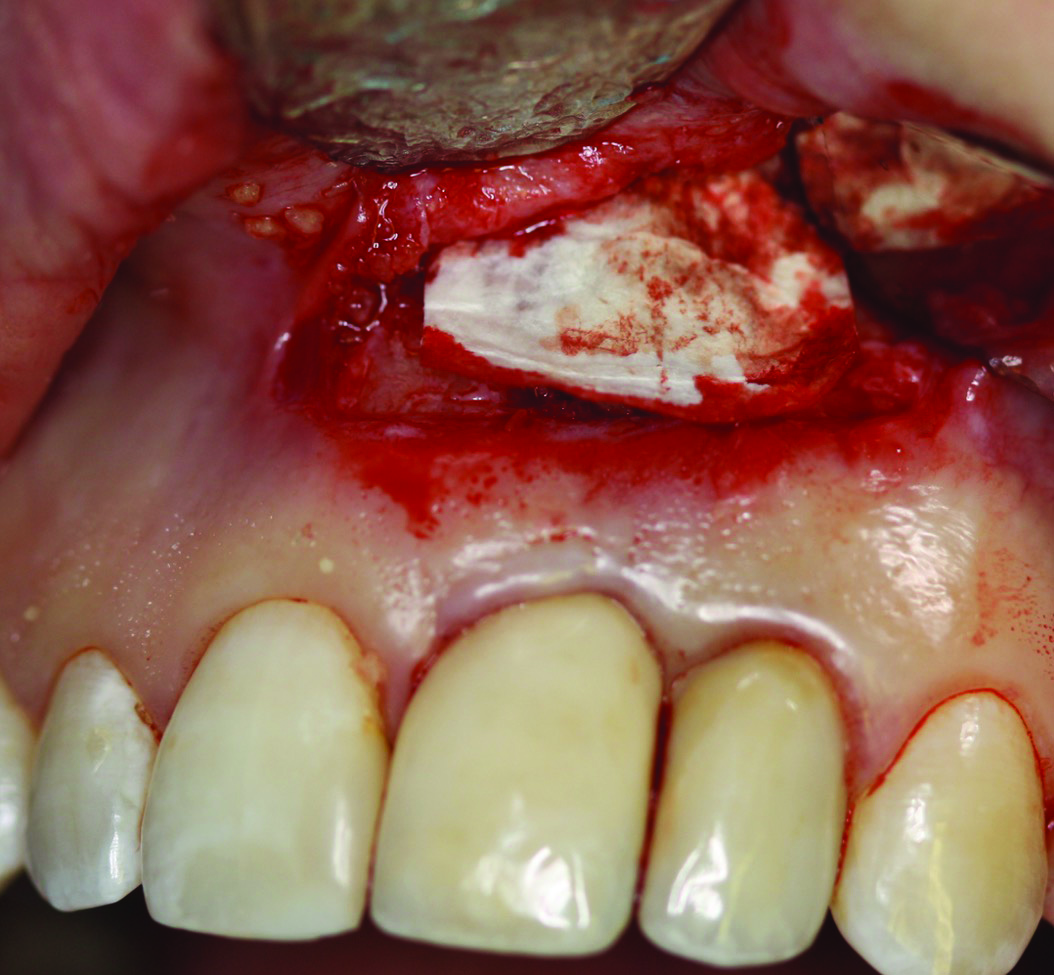

Fig 10. Case 2: FDBA bone allograft mixed with a small amount of doxycycline placed over the defect. The graft would be covered with a resorbable collagen membrane.

Figure 10

The patient in case 2 received a crestal incision with full-thickness flap elevation, then tooth No. 5 was extracted (Figure 9). Implant debridement followed the same protocol used in case 1. FDBA was mixed with a small amount of doxycycline and placed around the implant (Figure 10). A resorbable collagen membrane (not pictured) was secured with a tack. Primary closure was achieved with expanded polytetrafluoroethylene (ePTFE) sutures (Figure 11). An immediate post-surgical radiograph showed bone fill and the tack (Figure 12).